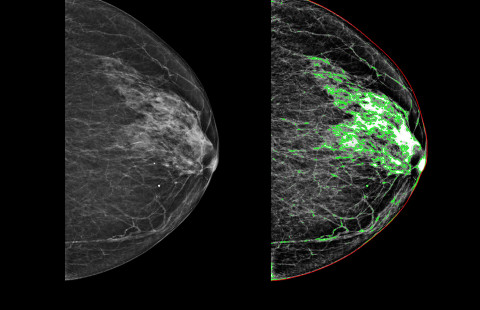

New drugs are constantly being developed for breast cancer. In the future, artificial intelligence will be used to assess individual risk for cancer. Liquid biopsy, on the other hand, reveals the risk of cancer recurrence.